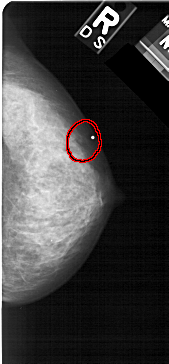

A_1472_1.RIGHT_CC

RIGHT_CC LINES 5086 PIXELS_PER_LINE 2356 BITS_PER_PIXEL 12 RESOLUTION 43.5 OVERLAY

FILE: A_1472_1.RIGHT_MLO.OVERLAY

TOTAL_ABNORMALITIES 1

ABNORMALITY 1

LESION_TYPE CALCIFICATION TYPE PLEOMORPHIC DISTRIBUTION CLUSTERED

ASSESSMENT 4

SUBTLETY 4

PATHOLOGY BENIGN

TOTAL_OUTLINES 1

BOUNDARY